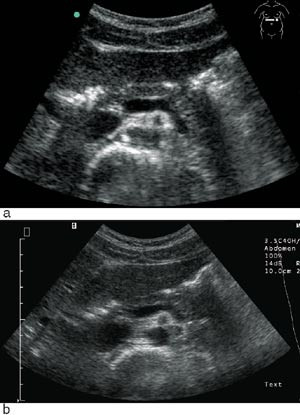

Undersøkerens totale tilfredshet med bruk av denne skanneren var: 0 lite tilfreds, 8 % litt tilfreds, 11 % moderat tilfreds, 36 % meget tilfreds, 45 % svært tilfreds. Skanneren var ikke bare egnet til «enkle» problemstillinger, men kunne også gi tilfredsstillende svar på mer kompliserte kliniske og bildemessige utfordringer (fig 3, fig 4).

Et sentralt spørsmål ved innføring av mobilt diagnostisk utstyr er om det leder til flere henvisninger eller om det kan avlaste spesialister og røntgenavdelinger. Data fra vår studie indikerer at behovet for å henvise videre til undersøkelse med en bedre skanner og høyere kompetanse kan ligge på omkring 14 %. Dette anslaget bekreftes av en annen studie, der initial skanning med bærbar ultralyd måtte gjentas med bedre skanner i 12 % av tilfellene (9). Diskusjonen om hvem som skal utføre ultralydundersøkelsen er imidlertid ikke ny (10), men det synes som om behovet for å henvise til et høyere nivå er omvendt proporsjonalt med kompetansenivået. Den viktigste begrensningen med denne bærbare skanneren er liten skjerm, noe som kan gi vanskelige synsforhold. Videre fant vi at vurderinger av parenkymatøse leversykdommer og tarmer gjøres best med en avansert stasjonær skanner.